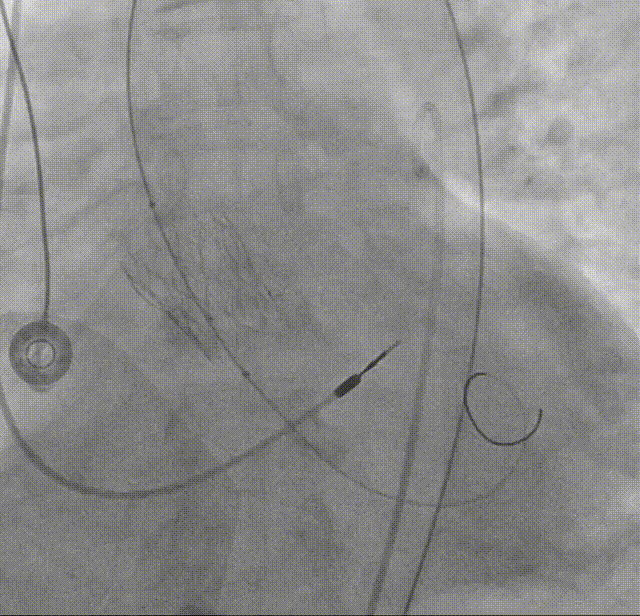

22mm球囊后扩:可见瓣膜形态明显改善

造影评估:瓣膜形态与位置理想,瓣周漏明显减少,导管测量跨瓣压差12mmHg

外周造影评估